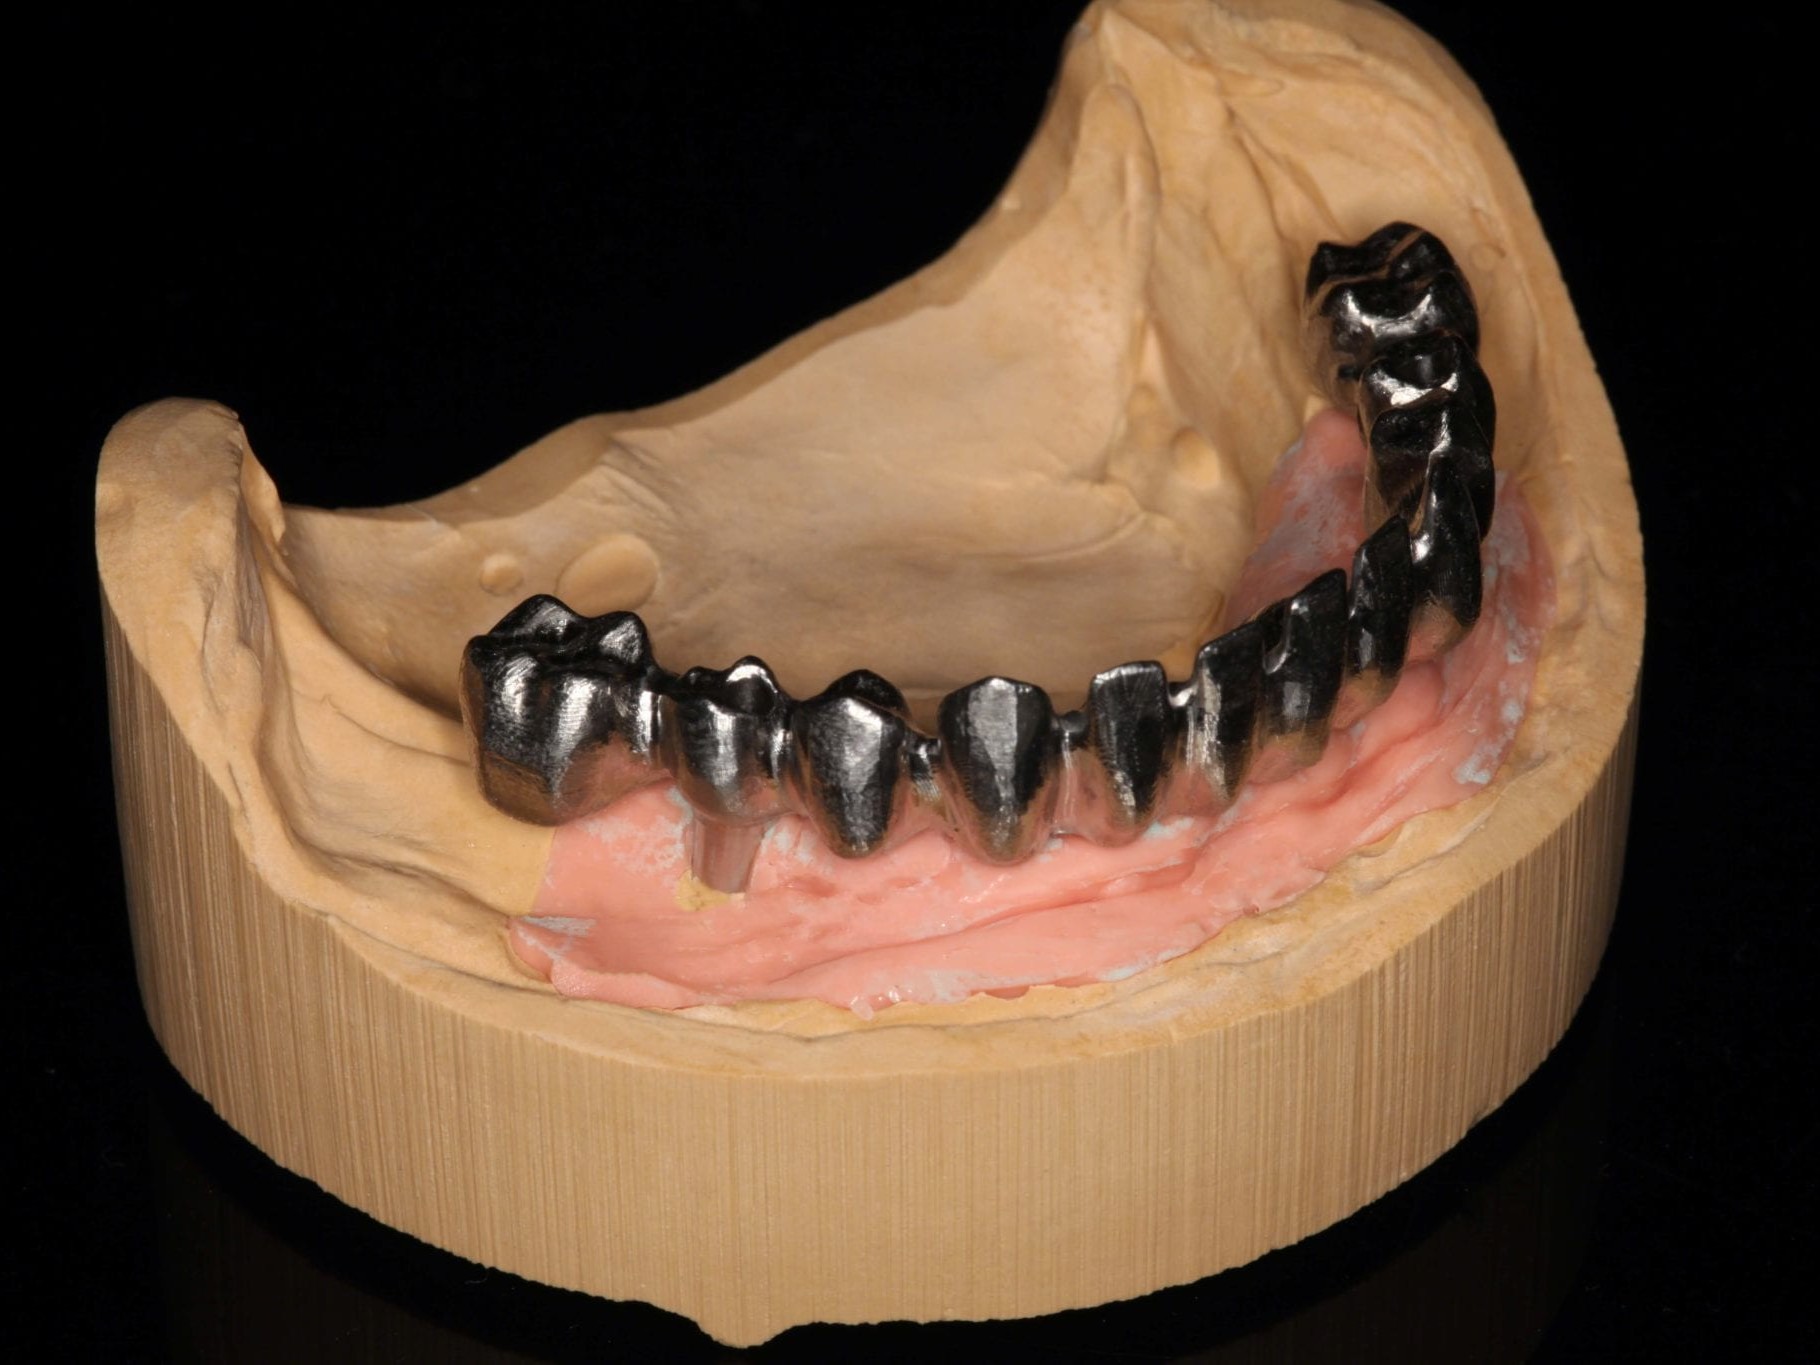

Die zweite Variante verzichtet auf eine erneute Abformung durch eine direkte Verblockung der Abformpfosten in der ersten Sitzung. Hierfür wird Zahnseide ohne Spannung mehrfach über Kreuz um die Abformpfosten gebunden. Das hieraus entstehende Gerüst dient als Trägerplattform für das Autopolymerisat. Das zeitversetzte Applizieren des Autopolymerisates gewährleistet die Spannungsfreiheit der Verblockung. Die Abformung erfolgte mit einem Polyether Abformmaterial in Doppelmischtechnik ⁴. Ebenfalls fertigte der Behandler in dieser Sitzung ein Zentrikregistrat sowie Laterotrusionsregistrate an. Das Meistermodell wurde aus Klasse–IV-Superhartgips mit typischer Gingivamaske hergestellt (Abb. 2). Durch das Vorgehen mit einer verblockten Präzisionsabformung lässt sich die höchste Genauigkeit bei weitspannigen Suprastrukturen erreichen. Diese Weitspannigkeit, bedingt durch das nach distal ausgedehnte prothetische Polygon, ist das Prinzip des SmartFix-Konzeptes. Nach der Modellherstellung erfolgte die anatomisch korrekte Übertragung der Schädel-Achs-Relation des Oberkiefers in den Artikulator ⁵ mittels Gesichtsbogen. Zur Montage des Unterkiefers konnte in diesem Fall auf eine klassische Bissnahme verzichtet werden, da das computerdesignte und okklusal verschraubte Langzeitprovisorium während der Einheilphase vom Behandler feinjustiert wurde und die Bisshöhe und -lage damit zur Übertragung perfekt geeignet war. Hierfür wurde vom Behandler das Provisorium entnommen, so dass der Zahntechniker in der Praxis die Einartikulierung unter Zuhilfenahme des vorher angefertigten Zentrikregistrates vornehmen konnte. Darüber hinaus wurde das Provisorium

mit einem Silikonwall auf dem Meistermodell dubliert. Die Individualisierung der Artikulatorenwerte erfolgte mit den Laterotrusionsregistraten

im Labor.

Der gesamte Workflow dieses Patientenfalles beruht auf dem Prinzip des Backward Planning. Sowohl bei der Chirurgie als auch bei der Prothetik ist dem Team aus implantatchirurgischen und implantatprothetischen Behandler und Zahntechniker daran gelegen, vorhersagbare Ergebnisse zu garantieren. Bei einer okklusal verschraubten Brücke ist es für den Zahntechniker vor Beginn der Arbeit wichtig, den späteren Austrittspunkt der Schraubenkanäle zu kennen und eine diagnostische Aufstellung in Form und Funktion anzufertigen. Nur so wird gewährleistet, dass das CAD/CAM gefertigte Gerüst optimal die Verblendungen unterstützt und die Schraubenkanäle ideale Durchtrittspunkte bekommen. Nach der Anfertigung der Aufstellung im Labor wurde der Patientenfall im ATLANTIS WebOrder Portal von Dentsply Implants angelegt und das Meistermodell mit der diagnostischen Aufstellung an die ATLANTIS ISUS Produktion nach Belgien geschickt. Die Durchführung und Digitalisierung des Meistermodells und die Erarbeitung eines Designvorschlages für das anatomisch reduzierte Brückengerüst erfolgte unter Verwendung einer speziellen CAD–Software. Obwohl der Designprozess in diesem Schritt zumindest nicht direkt in den Händen des Zahntechnikers liegt, bedeutet es aus Sicht der Autoren nicht den Verlust von Kompetenz oder Designfreiheit. Auch hier gilt: Bevor eine Arbeit in die zentrale Fertigung geht, benötigt sie die Freigabe durch den Zahntechniker. Das ATLANTIS ISUS Team geht auf die Änderungswünsche des Zahntechnikers ein und unterbreitet weitere Designvorschläge, bis ein Vorschlag perfekt ist und akzeptiert wird. Die auf den zehntel Millimeter genau festzulegende Reduktion des Gerüstes (Abb. 3) richtet sich nach der Indikation der Verblendung.